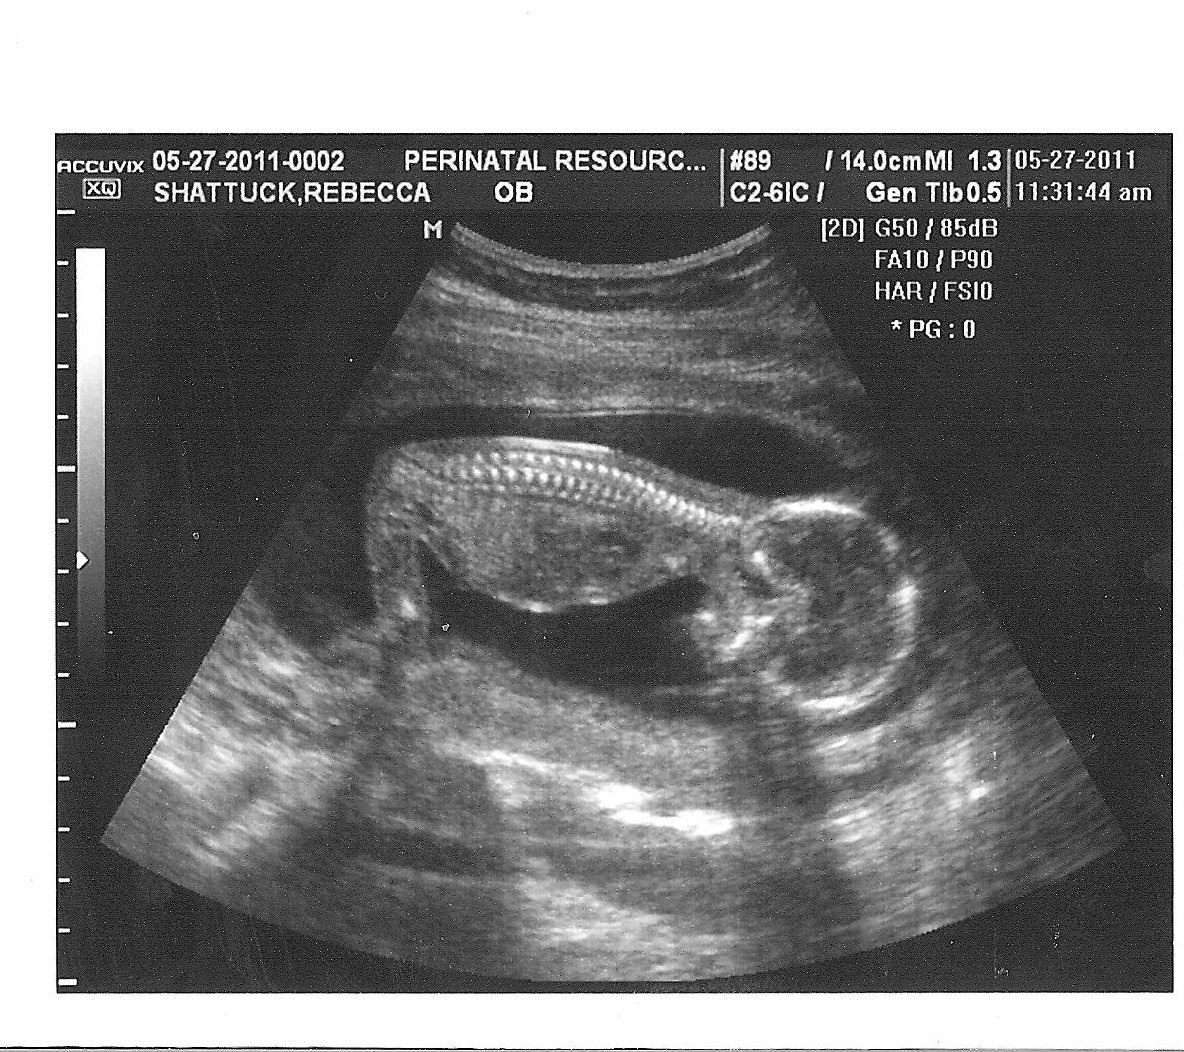

what does a boy look like on ultrasound

Ultrasound at 12 weeks 2 days! Found out that it’s a boy! Can’t wait to …

The Best Baby Boy Ultrasound Pictures 13 Weeks Listen here – Baby Boy …

Boy or Girl? 13 week ultrasound liked on Polyvore featuring babies …

Week 13 Ultrasound – Boy or Girl?

12 Week Ultrasound – Boy or Girl?

How To Tell Gender On Ultrasound At 12 Weeks

Ultrasound Baby 12 Week Pregnancy – babypregnancy